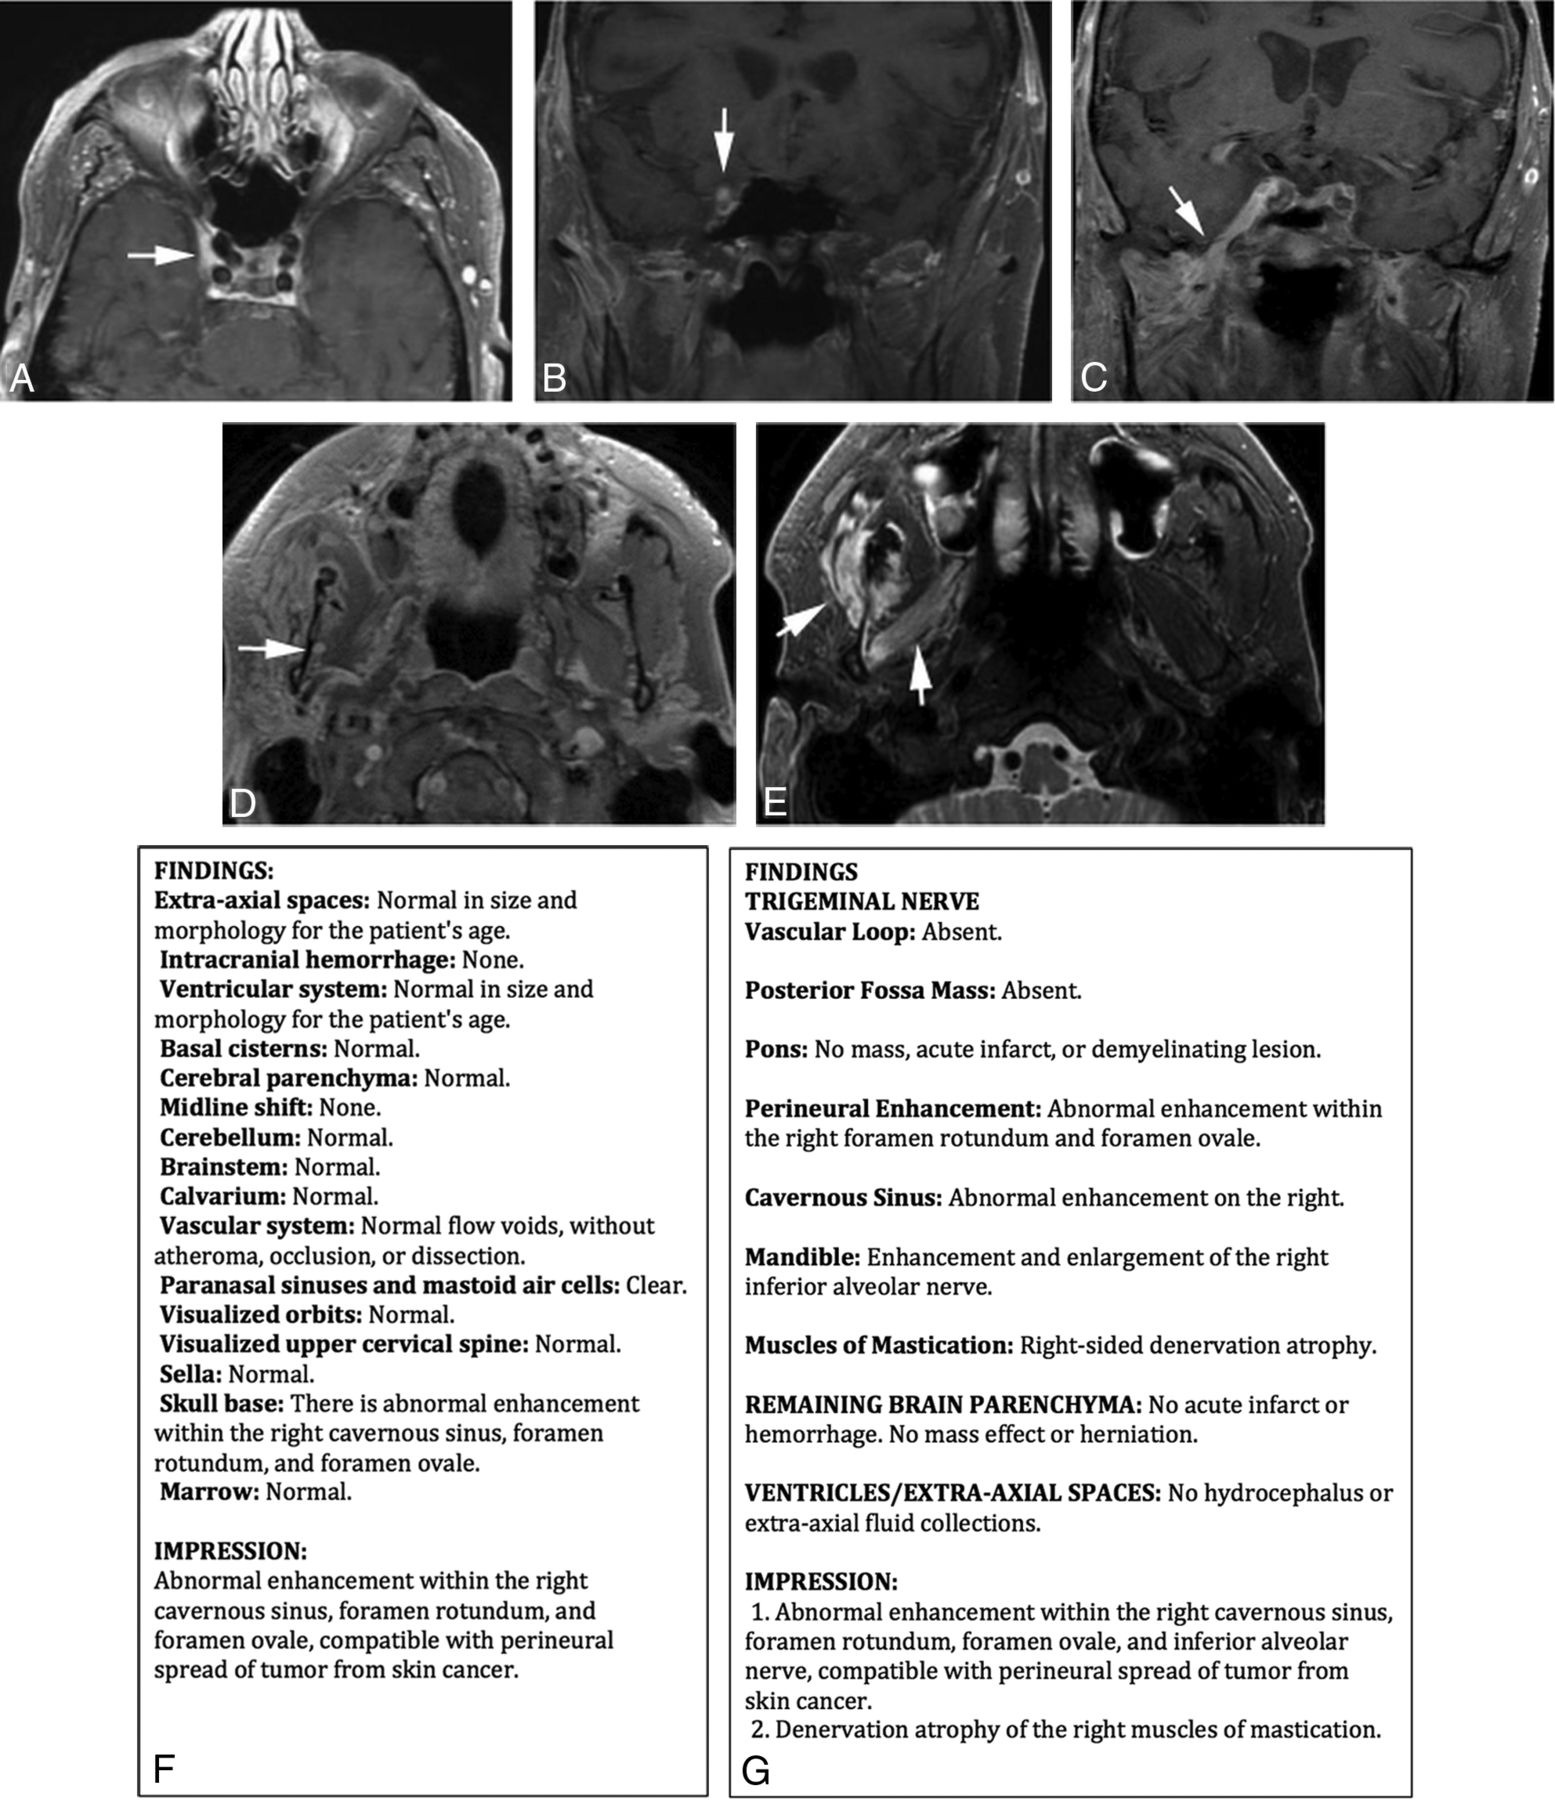

The imaging work-up of trigeminal neuralgia necessitates careful inspection for pathologies extending from the brain stem to the mandible. A contextual template facilitates this detailed evaluation in a succinct manner. The radiologist will remember where to identify potential causes, and the referring provider will be satisfied that the main diagnostic causes were assessed. Conversely, traditional free text or noncontextual structured templates could omit commentary on important elements and could also address unnecessary items, thereby cluttering the report. Figure 5 highlights this difference using a noncontextual structured template12 versus a contextual template for trigeminal neuralgia.

Value of a contextual structured template for trigeminal neuralgia over a noncontextual structured template. A–D, Axial and coronal contrast-enhanced fat-suppressed imaging in a patient with skin cancer shows extensive perineural enhancement (arrows). E, Axial fat-suppressed T2-weighted image shows denervation atrophy in the right muscles of mastication (arrows). A noncontextual structured template (F) and a contextual structured template (G) describe the findings. Note that the noncontextual template is unnecessarily lengthy, and the skull base field is the only field conceivably relevant to trigeminal neuralgia, as opposed to the multiple relevant fields within the concise contextual template. Furthermore, discussion of the inferior alveolar nerve enhancement and muscular denervation atrophy could have been overlooked in the noncontextual template because there are no fields to describe them.